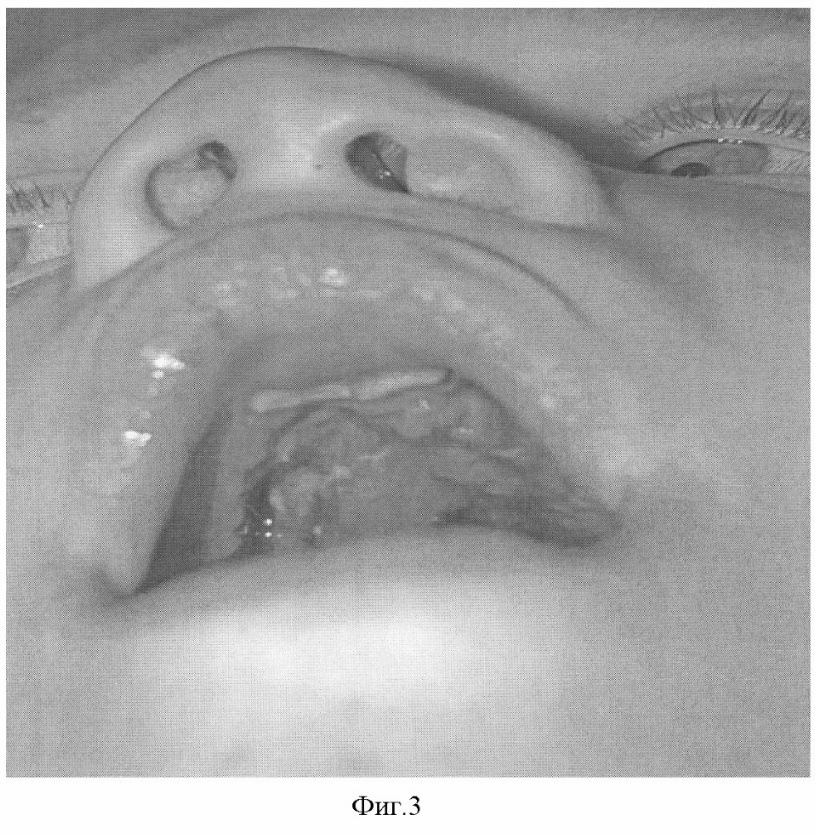

Пример. Больной Д., 5,5 лет, обратился в клинику по поводу послеоперационного дефекта среднего и переднего отдела твердого неба. Ранее оперирован по поводу врожденной полной правосторонней расщелины твердого и мягкого неба, дважды – по поводу послеоперационного дефекта твердого неба (фиг.1). Под эндотрахеальным наркозом выкроены трапециевидные слизисто-надкостничные лоскуты по обе стороны дефекта, которые мобилизованы, ротированы в сторону носовой полости, нижний лоскут деэпителизирован, на раневую поверхность верхнего лоскута (фиг.2) и деэпителизированную поверхность нижнего установлены сетчатые имплантаты с размерами ячейки от 4×4 мм, изготовленные в соответствии с их конфигурацией из никелид-титановой нити, толщиной 60 мкм, верхним рядом узловых швов имплантаты фиксированы между собой, нижним – мягкие ткани, дополнительная фиксация осуществлена йодоформными полосками и съемной защитной пластинкой. Послеоперационное течение гладкое, швы сняты спустя 10 суток. Заживление ран – первичное (фиг.3). Рекомендовано наблюдение у ортодонта и лечение у логопеда. При осмотре через 6 месяцев отмечены хорошие анатомические и функциональные результаты.